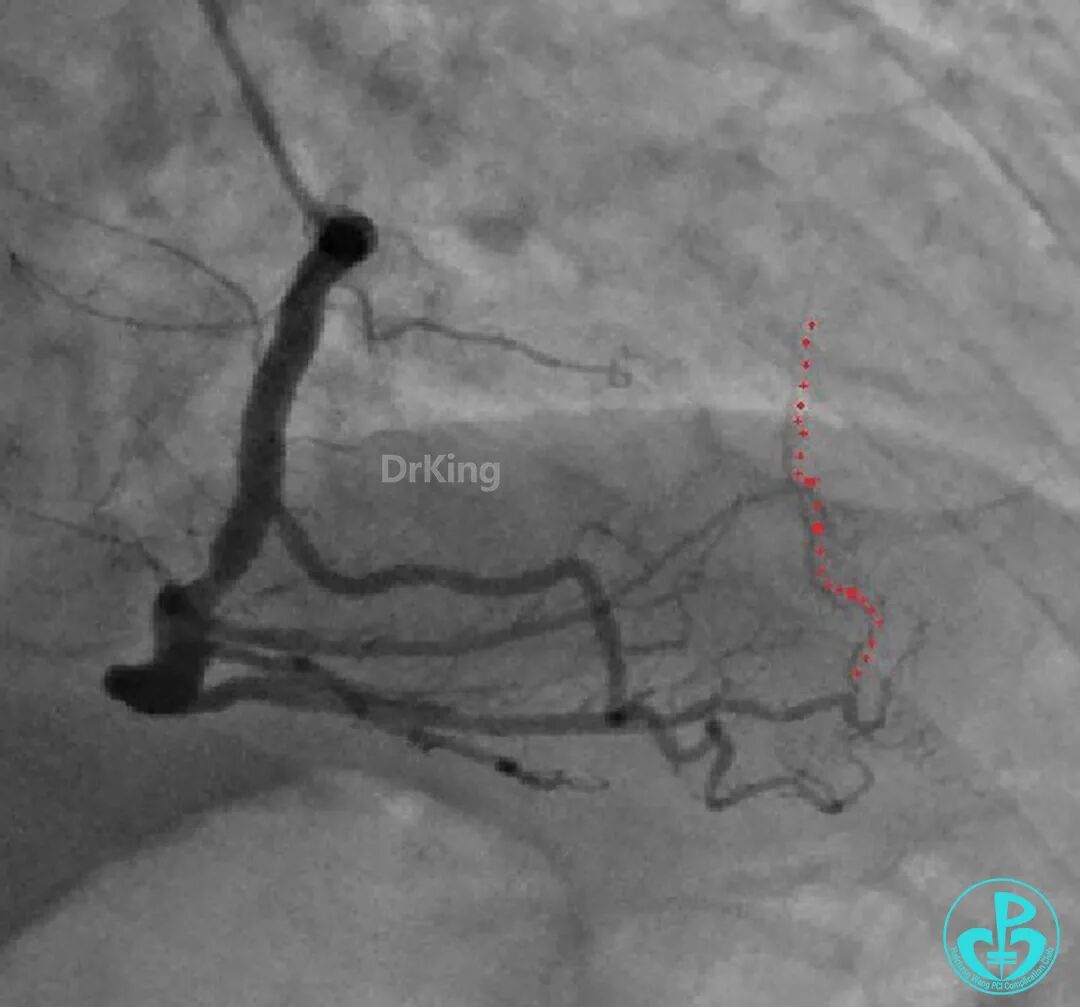

再次上台造影,钝缘支分支远端弹簧圈封堵处仍然有造影剂外漏。

明胶在血管怎么降解并发症丨前降支CTO同侧逆向开通时侧支血管破裂,弹簧圈联合明胶海绵封堵_https://www.jmylbn.com_新闻资讯_第48张

明胶在血管怎么降解并发症丨前降支CTO同侧逆向开通时侧支血管破裂,弹簧圈联合明胶海绵封堵_https://www.jmylbn.com_新闻资讯_第49张

心包穿刺引流。

2根导丝进入到钝缘支分支远端,1根导丝送入微导管,另外1根导丝送入2.5×15mm球囊,2.5×15mm球囊远端Marker与微导管齐口(自制OTW球囊),经微导管缓慢推注明胶海绵糊。

明胶在血管怎么降解并发症丨前降支CTO同侧逆向开通时侧支血管破裂,弹簧圈联合明胶海绵封堵_https://www.jmylbn.com_新闻资讯_第51张

明胶在血管怎么降解并发症丨前降支CTO同侧逆向开通时侧支血管破裂,弹簧圈联合明胶海绵封堵_https://www.jmylbn.com_新闻资讯_第52张

钝缘支分支远端破口完全闭塞。